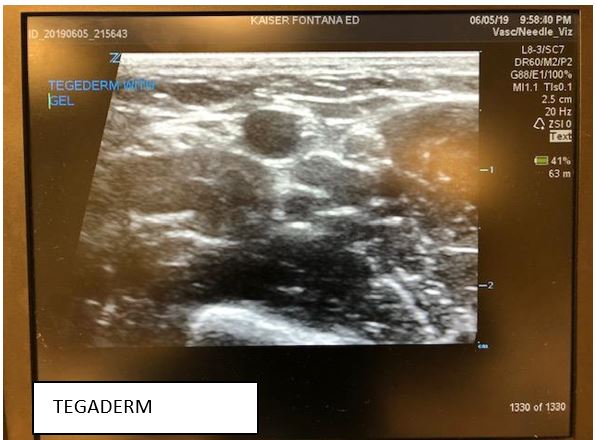

Recently, the ultrasound community has seen a great debate spanning across various social media outlets, email, and academic arenas about the use of Tegaderm and its potential for damaging and degrading the rubber surface of the ultrasound probe over time. For many of us, we can remember our early days of residency when ultrasound-guided IVs first came into practice. Many people may not have even used a Tegaderm when first learning how to do this technique. Later, they discovered that covering the probe surface with a tegaderm or using sterile/nitrile gloves as a probe cover provided a cleaner surface than doing the IV line with just gel and the probe alone.1,2 This cleaner method was also more cost-effective than using the more commercially-available sterile probe covers. However, in the last year, there has been increasing concern regarding the potential risks associated with using a Tegaderm.

Parker labs introduced the UltraDrape an affordable, sterile dressing that acts as a barrier against contamination. Since a probe cover is not required, gel is placed on the top surface of the dressing, separating the probe from the sterile gel-free puncture site. This top layer is later removed and the remaining adhesive layer below acts to secure the IV reducing clean up time, contamination, and mess associated with excess gel. However, this product requires that you view and mark where you will be inserting the IV before placing the UltraDrape down since it can’t be moved once you set it down. Views of the vessel on the machine are comparable to using tegaderm and it costs $2.50 per dressing.